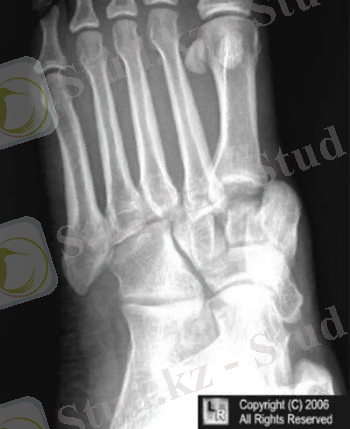

10-сурет: Лисфранк буынында сол жақтан біржақты толық шығуы

Жарақат механизмі: тура (табанның алдыңғы бөліміне соққы не құлау) Табан сүйектерінің жекеленген сынықтары үшін ығысу аса тән емес, көптеген сынықтар ығысумен жиі жүреді.

Диагностикасы: табанның сыртқы бетінде ауырсыну және ісіну. Табан сүйектеріне осьті жүктеме және жергілікті пальпация ауырсынумен жүреді. Якобсон симптомы -табан сүйегі басын басқанда сынған жерде ауырсыну.

Радиологиялық зерттеу: Екі проекцияда жүргізіледі

Емі: Табан сүйектерінің ығысусыз сынықтарында консервативті ем: 4-6 аптаға сирақтың төменгі үштен біріне дейін гипсті таңу салу.

Ығысумен болған сынықтар кезінде Черкес-Заде рамасында қаңқадан тарту, яғни сәйкес тырнақ фалангасынан тракция жасау. Бұл кезде жансыздандырғаннан кейін тырнақ фалангасына біз өткізіп рамаға бекітіледі және рама гипсті таңуға бекітіліп тұрады(10 сурет) Клапп бойынша тарту тырнақтық фалангадан арнайы шоттың(цапка) көмегімен жүргізіледі(11 сурет) Қаңқадан таруды 3-4 аптадан соң шешеді.

10-сурет: Черкес-Заде бойынша табан сүйектерінің сынықтарын емдеу